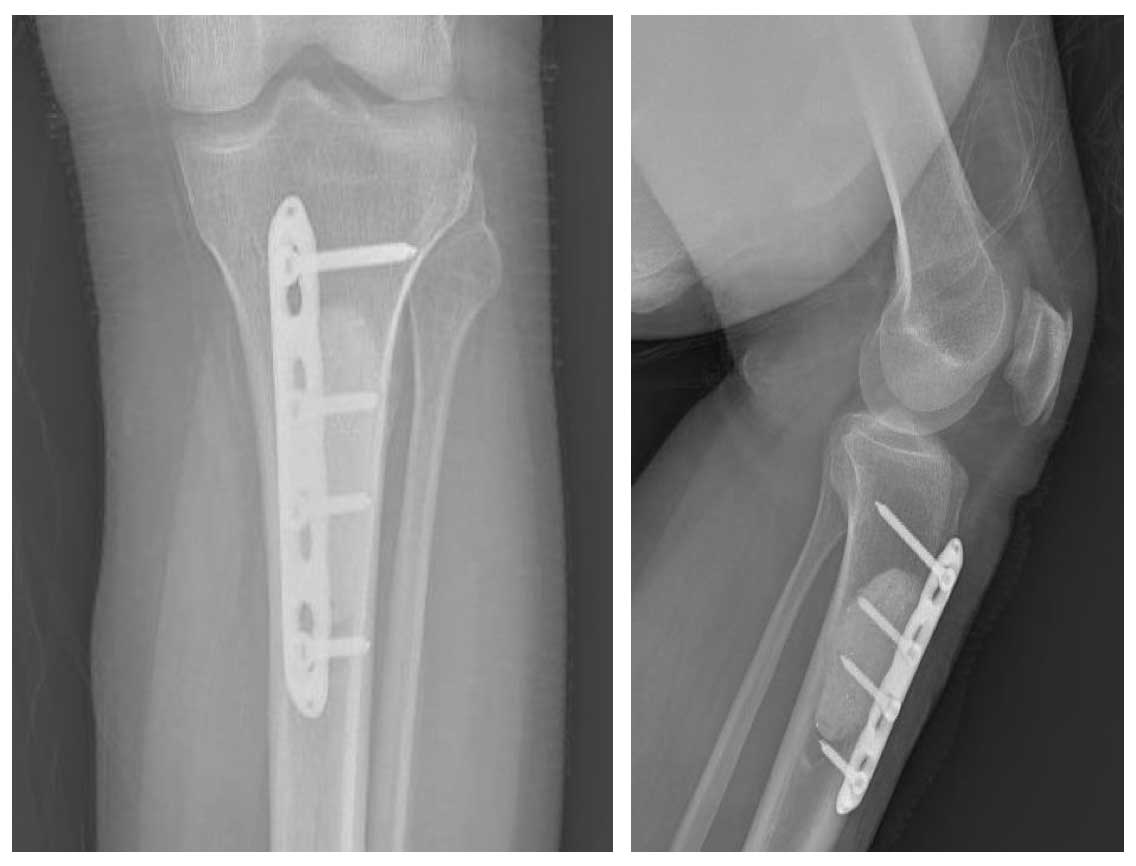

Ameliyat Sonrası: Röntgende temizlenen tümör yerine uygulanan kemik çimentosu ve plak ile fiksasyon görülmekte.